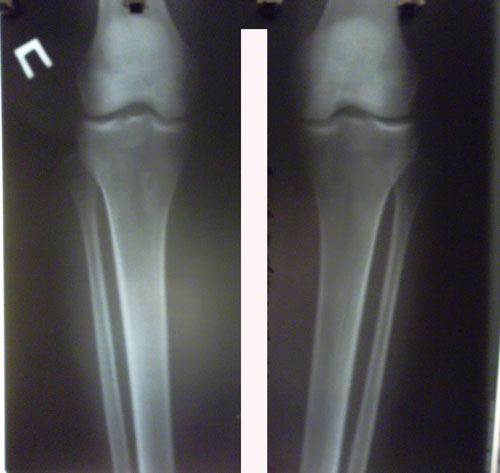

Исходник - 35 лет.

Укорочение правой ноги - 2 см.

Левая голень более деформирована.

Дата снятия аппаратов 22.06.2016г.

Срок лечения 90 дней.

Диагноз: Укорочение правой ноги - 2 см.